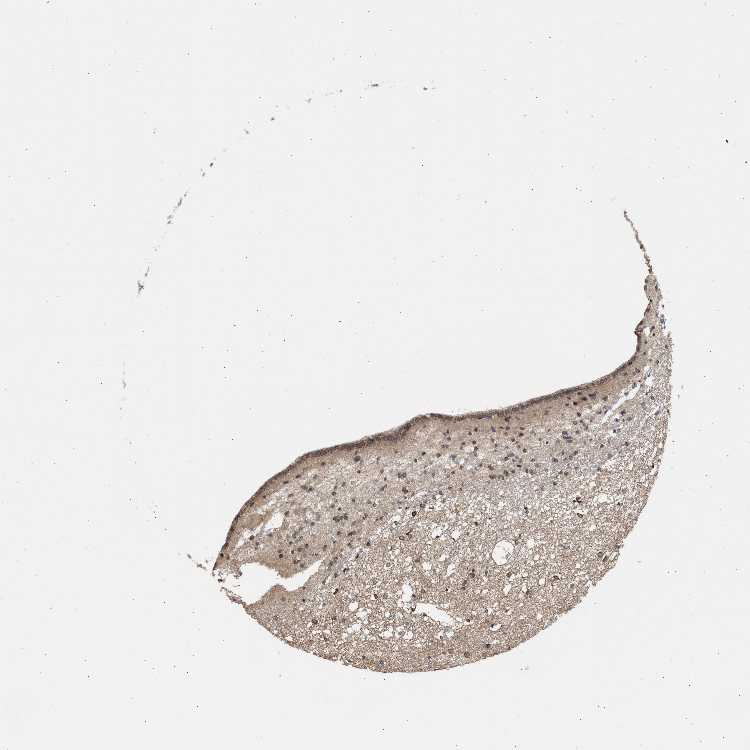

BRAIN BASAL GANGLIA Show tissue menu

BASAL GANGLIA - Expression summary

Protein expression

On the top, protein expression in current human tissue, based on all annotated cell types, is reported with the units not detected (n), low (l), medium (m) and high (h). Underneath, protein expression in each annotated cell type are reported using the same units.

Protein expression data is based on knowledge-based annotation. For genes where more than one antibody has been used, a collective score is set.

Glial cells: Low

Neuronal cells: High

CAUDATE - Antibody stainingi

Antibody staining in the annotated cell types in the current human tissue is reported as not detected, low, medium, or high, based on conventional immunohistochemistry profiling in selected tissues. This score is based on the combination of the staining intensity and fraction of stained cells.

Each image is clickable and will lead to virtual microscopy that enables deeper exploration of all samples and also displays staining intensity scores, fraction scores and subcellular localization as well as patient and tissue information for each sample.

Antibody HPA005435Antibody CAB020724

Glial cells HighLow

Neuronal cells -High